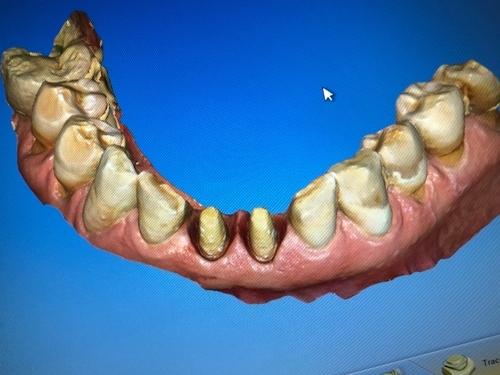

Il manufatto che sostituisce i denti mancanti o che ricopre denti distrutti, si chiama protesi dentaria che può essere fissa o mobile a seconda se è una protesi che si deve togliere per essere pulita(protesi mobile), o se è una protesi fissa cioè cementata o incollata ai denti adiacenti nel caso di un ponte o direttamente ai denti compromessi che necessitano di essere ricoperti.Con una tecnica all'avanguardia, si prende l'impronta non più in maniera tradizionale ma passando in bocca uno scanner che trasferisce l'impronta sul computer e li si riesce a progettare e fresare capsule monolitiche in pura porcellana, senza metallo che potrebbe creare allergie.

Qui sotto nelle foto,si vede la prima foto(a sinistra)dell'impronta trasferita al computer,la seconda(a destra)foto la progettazione e la terza foto (sotto a sinistra)le capsule provvisorie(in resina Telio) cementate in bocca.Dopo un mese viene ripresa l'impronta e progettate le capsule definitive in porcellana che vengono incollate ai denti formando con essi un corpo unico

Un paziente adulto si è presentato nel nostro studio per correggere questa malposizione dei denti dell'arcata superiore ed dell'arcata inferiore. Dopo un attendo studio abbiamo deciso di procedere con la terapia di correzione attraverso l'utilizzo di mascherine trasparenti (F22). Il risultato è stato come noi l'avevamo proposto ed il paziente è rimasto molto soddisfatto del risultato ottenuto. Le foto qui sotto lo testimoniano.

Le foto a sinistra arcata superiore sopra e arcata inferiore sotto prima del trattamento.

Le foto a destra dopo lo studio e il trattamento.